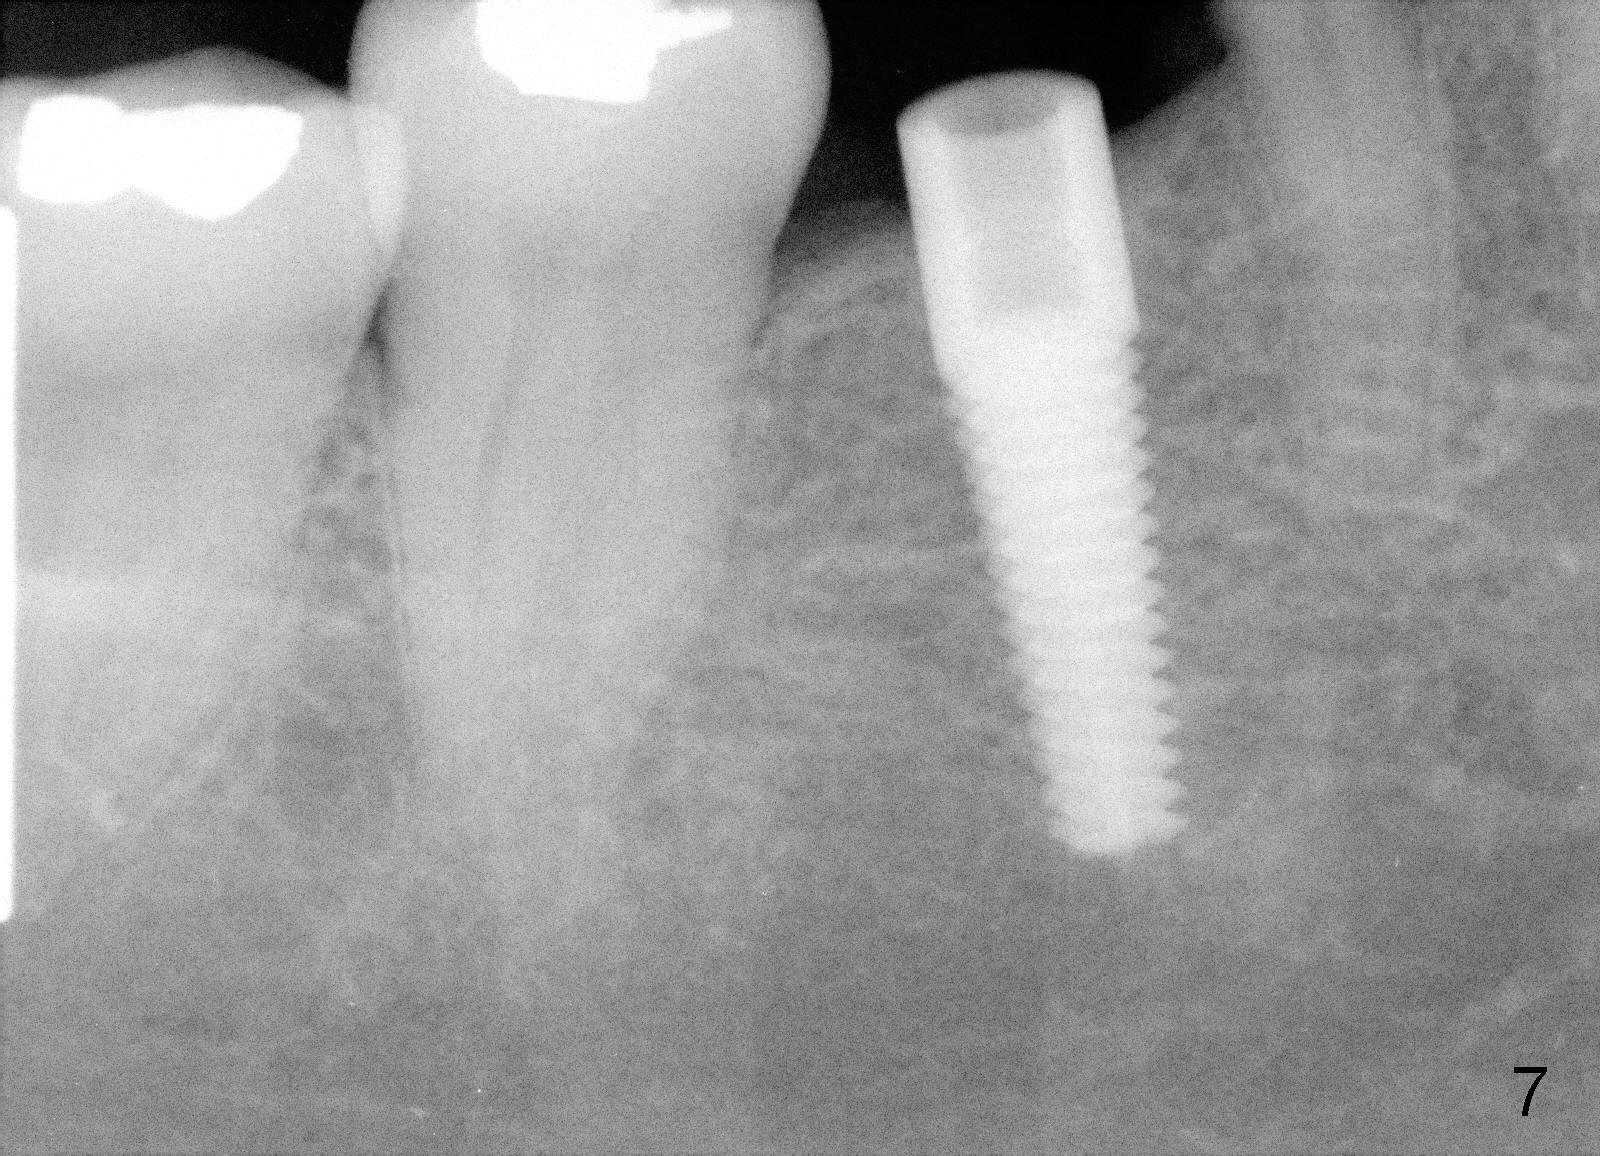

Due to unavailability of bone-level implant, a tissue-level implant is to be placed as a backup (Fig.1: 4.5x17 mm). Osteotomy is initiated with 1.5 mm pilot drill at depth of ~ 10 mm; the trajectory appears to be as good as expected (Fig.2). Osteotomy is gradually increased to 4.5x17 mm, followed by insertion of 4.5x17 mm tap (Fig.3,4). The ostetomy appears to be deviated lingual (Fig.5). When the tap is removed, the buccal plate appears to be thin (Fig.6). A tapered implant is placed (Fig.7).